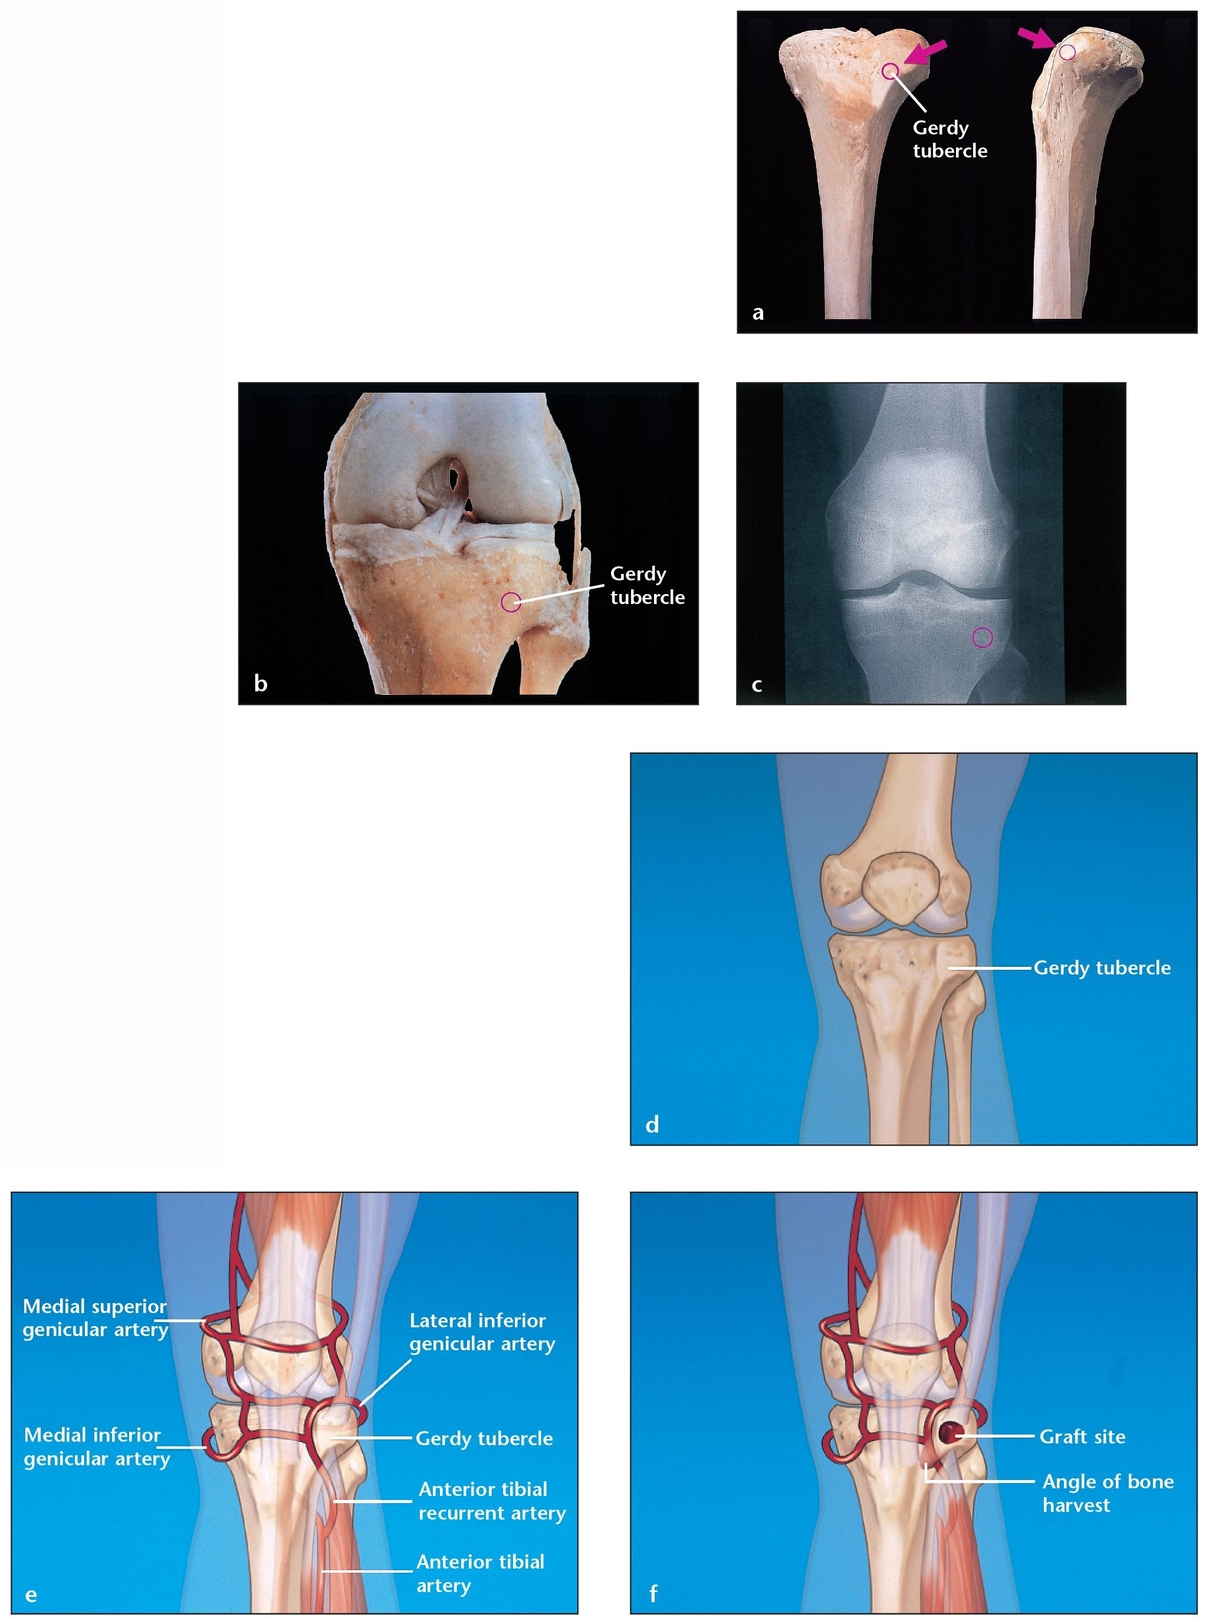

최근에는 동종골 이식 뼈 기술이 많이 발전하긴 했지만, 자가골 이식의 골생성이나 유합정도를 이기기는 힘듭니다. 주로 이식을 위한 뼈는 경골, 비골, 장골 에서 채취하게 됩니다. 아무래도 이러한 뼈 채취부위의 특징은 회복이 빠르고, 구조적인 장점을 가지며 골생성 능력도 좋은 부분 입니다.

1. 경골